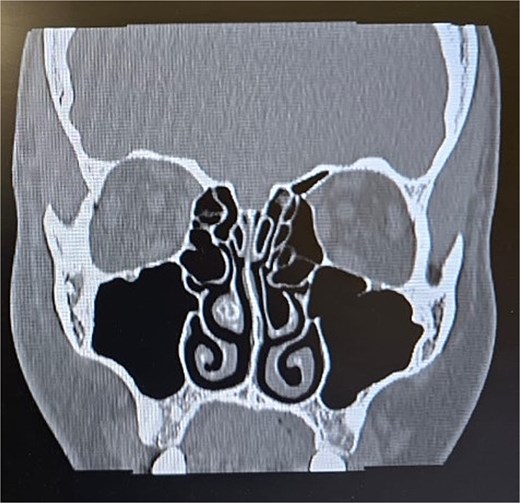

Clinical examination, including anterior rhinoscopy and nasal endoscopy, revealed a midline nasal septum and bilateral hypertrophy of the inferior and middle turbinates, with otherwise normal nasal mucosa. A CT scan of the paranasal sinuses in the coronal plane demonstrated bilateral pneumatization of the middle turbinates consistent with CB. Additionally, the right inferior turbinate was pneumatized, with communication to the ipsilateral maxillary sinus (Figs 1 and 2).

Paranasal sinus CT scan in the coronal plane demonstrating bilateral inferior concha bullosa with communication to the maxillary sinuses.